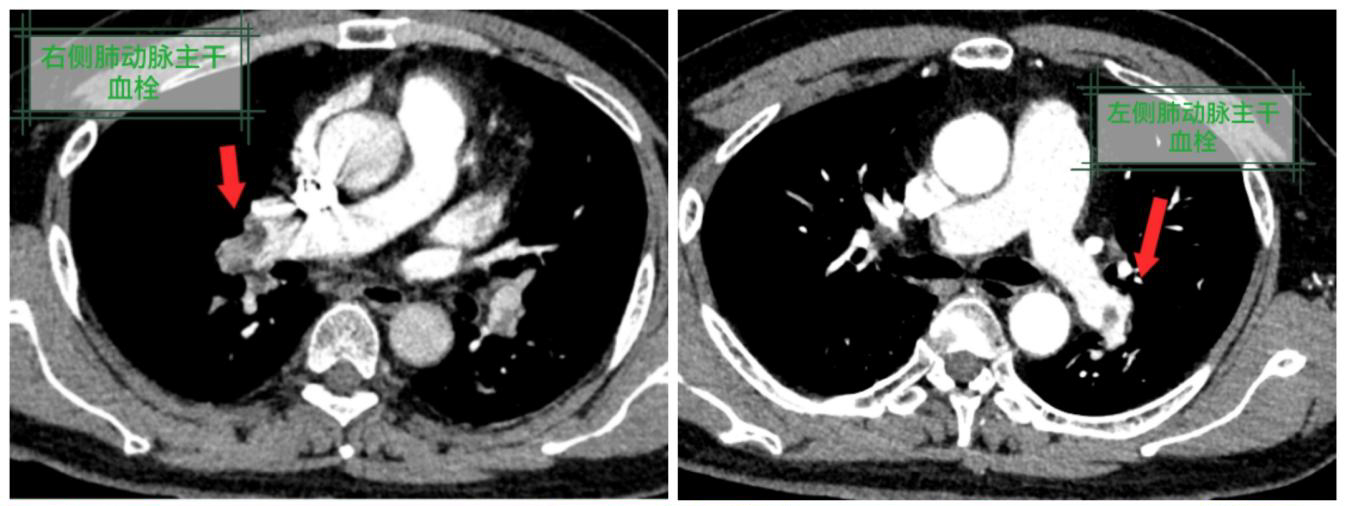

总院呼吸与危重症医学科团队在接到转诊患者后迅速响应,立即为患者完善相关检查。“该患者确实属于极危重情况,经检查明确诊断为:肺动脉主干及多发分支栓塞(中高危),合并双侧髂静脉血栓、呼吸衰竭,血栓负荷极重,下腔静脉近乎完全堵塞。若救治稍有延误,猝死风险极高!”